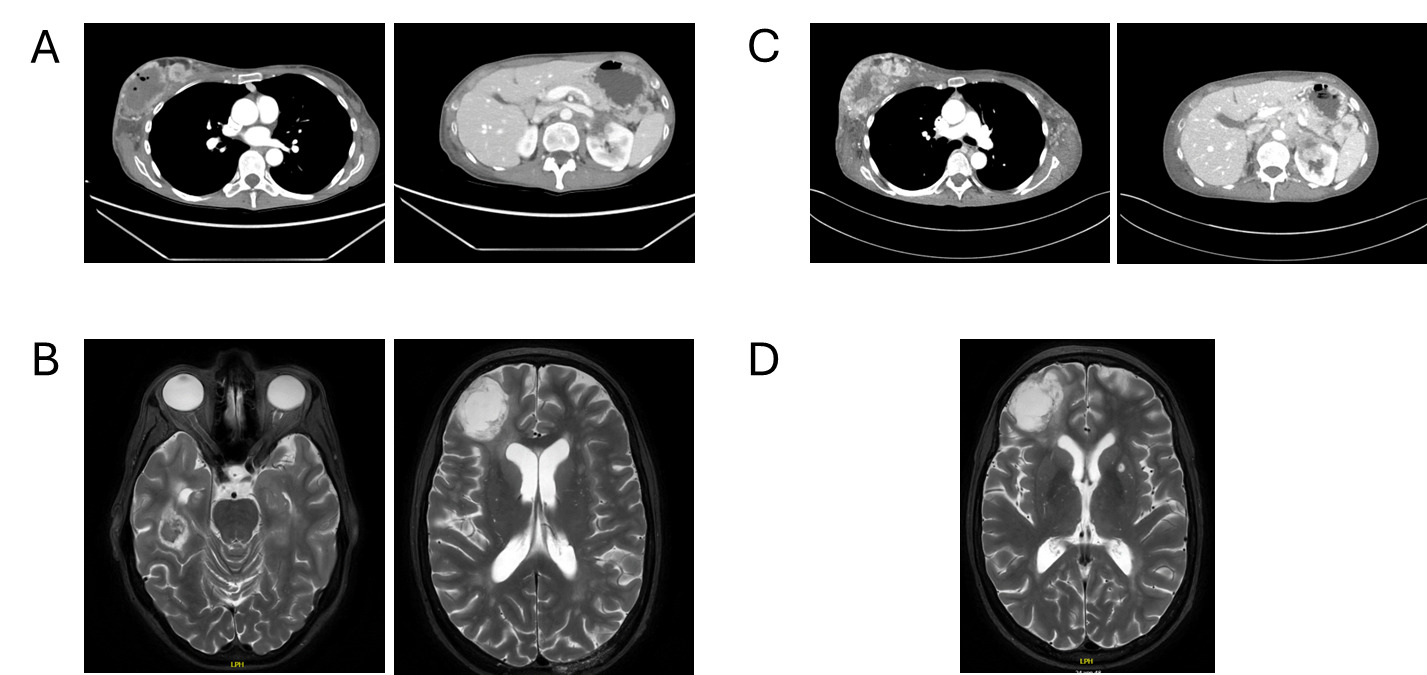

Follow-up in March 2025 showed a marked treatment response after two cycles, with significant regression of intracranial metastases on brain MRI, including resolution of midline shift and cerebral edema, as well as pronounced regression of nodal and visceral disease on contrast-enhanced CT of the thorax and abdomen (Figures 3A and 3B). No new metastatic lesions were identified, consistent with substantial partial remission.

During ongoing treatment, exulceration of the right breast primary tumor developed, indicating an early sign of further disease progression. Initially, it was managed conservatively with oral amoxicillin plus clavulanic acid and referred to specialized wound care. In May 2025, after four cycles of treatment, contrast-enhanced CT and cerebral MRI revealed disease progression involving systemic and intracranial sites (Figures 3C and 3D). Concurrently, thrombosis of the left external iliac vein and new segmental pulmonary emboli in the left lower lobe were detected and therapeutic anticoagulation with apixaban was initiated. Given the radiologic progression on paclitaxel plus pembrolizumab, carboplatin monotherapy was started as an interim measure while reimbursement approval for targeted therapy was pending. However, chemotherapy was discontinued after a single administration at the patient’s request.